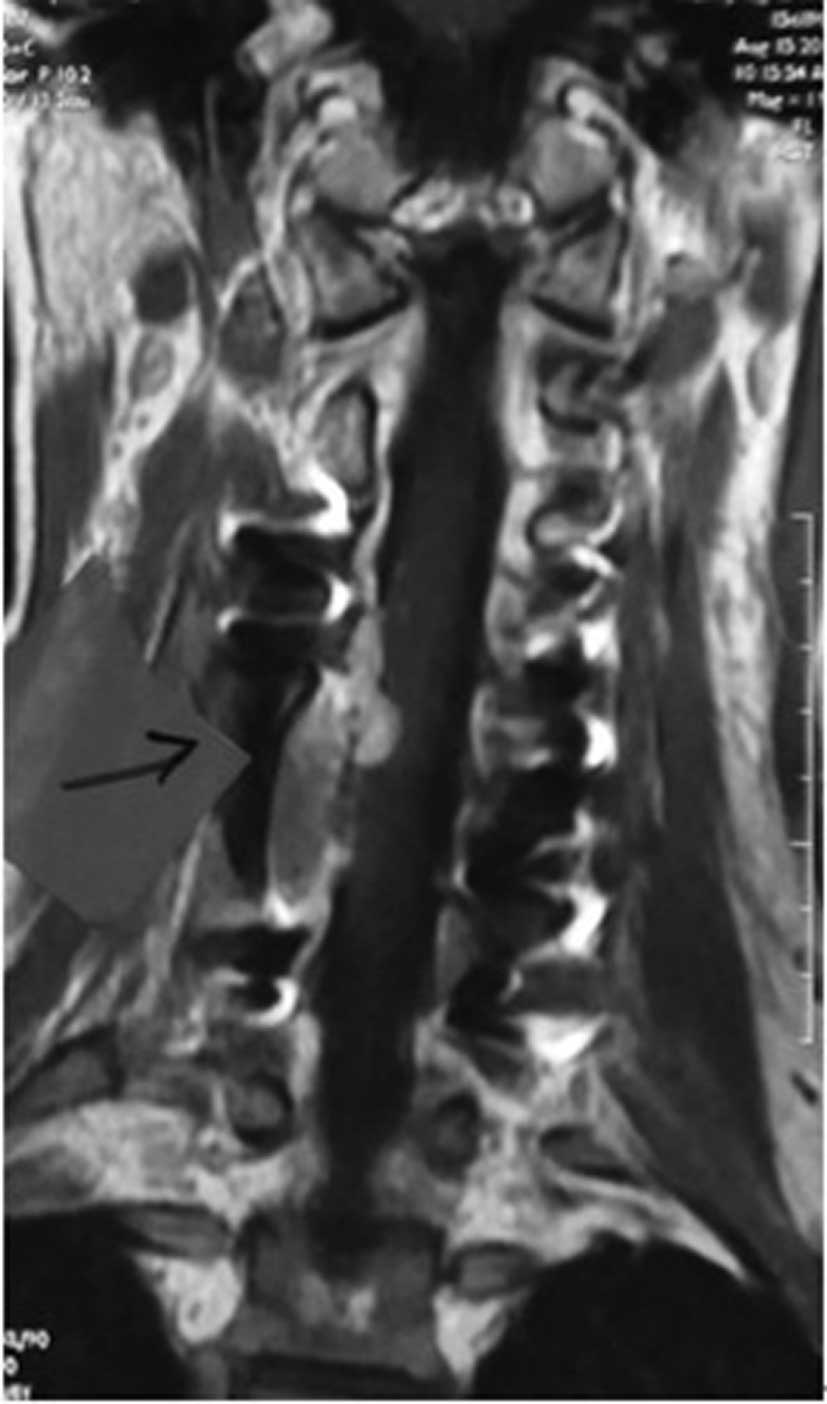

Primary dumbbell-shaped Ewing's sarcoma of the cervical vertebra in adults: Four case reports and literature review

Ewing's sarcoma is the second most common malignant bone tumor in children and adolescents. The 4 cases described in this study were diagnosed with dumbbell-shaped intraspinal and extraspinal Ewing's sarcomas. The incidence of dumbbell-shaped tumors of this type in the spine is 17.5%. These tumors are often misdiagnosed as neurogenic tumors (schwannoma, neurofibromatosis) or giant cell tumors based on imaging. Radiculopathy is more common than spinal cord compression in Ewing's sarcoma. Preoperative biopsy is strongly recommended. As soon as Ewing's sarcoma is diagnosed by pathology, the treatment should begin with 2-3 cycles of neoadjuvant chemotherapy. Anterior-posterior and posterolateral approaches are both recommended for exposing this tumor. Following surgery, chemotherapy is critical to lessen the rate of recurrence and metastasis and to prolong the survival time. However, radiotherapy should be used with caution, as the spinal cord is sensitive to radiation; local irradiation is suggested. The tumor is difficult to remove en bloc in the cervical spine. It has a high rate of recurrence and metastasis. Therefore, the prognosis of Ewing's sarcoma in the cervical region is poorer compared to that in the thoracic and lumbosacral regions.